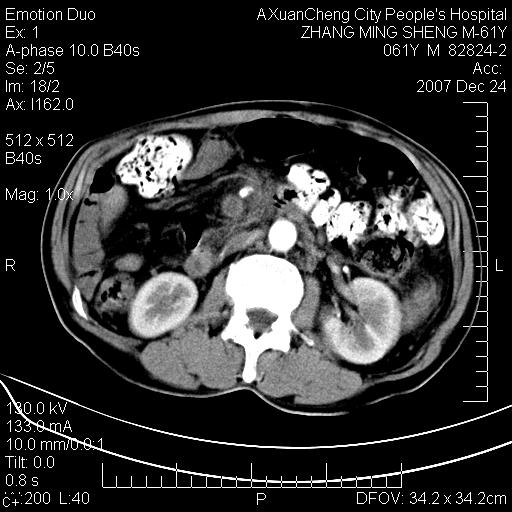

标题: CT11031:M61Y,胰腺占位

大家侃侃门静脉和胆管系统怎么回事,肝内转移?

胰腺癌肝转移

2,肝内多发结节状低密度占位,伴门脉及肠系膜上v栓子形成.考虑a;门脉及肠系膜上v血栓后肝改变.b;弥漫型肝癌伴门脉及肠系膜癌栓.

肝硬化,门脉高压,脾肿大;弥漫性肝癌,肝内、门脉、腹膜后淋巴结转移,肝内外胆管扩张,胰头区占位,建议mr检查

胰腺癌伴肝内转移;门脉、肠系膜上v癌栓形成。

考虑为:胰腺癌伴肝脏转移、腹膜后淋巴结转移,门静脉及肠系膜上静脉瘤栓形成。

胰体尾癌伴肝内转移,门静脉及肠系膜上静脉瘤栓形成.